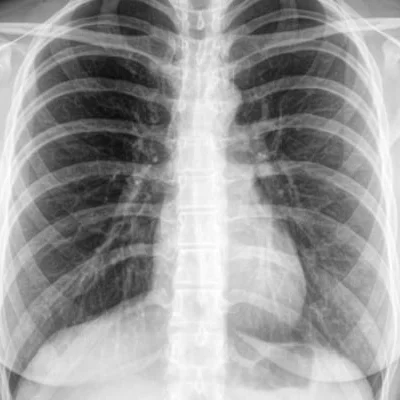

Chest X-Ray

Used to detect pneumonia, tuberculosis, lung nodules, and heart enlargement.